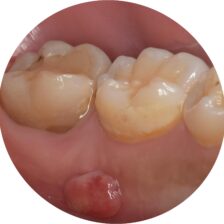

本当に根管治療が必要か?必要だとしてどの歯が原因なのか?

各種精密な診査を行い説明を行います。

また、根管治療によりどのくらいの成功率で残せるのか?

当院では世界的なエビデンスデータを用いながら当院オリジナルの治療実績も踏まえてご説明いたします。